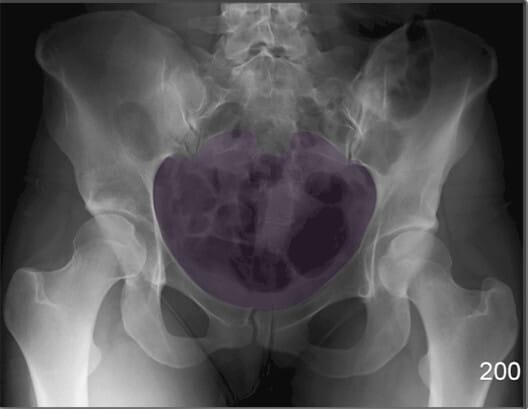

골반 입구 (Pelvic Inlet)

| 골반 입구 (Pelvic Inlet) |

| ✅ 천골 윗면에서 치골결합까지 이어지는 경계로, 출산 시 태아가 처음 통과하는 공간입니다. |

| 🔴 AP view에서는 전체 골반 윤곽과 함께 전후 직경을 간접적으로 추정할 수 있습니다. |